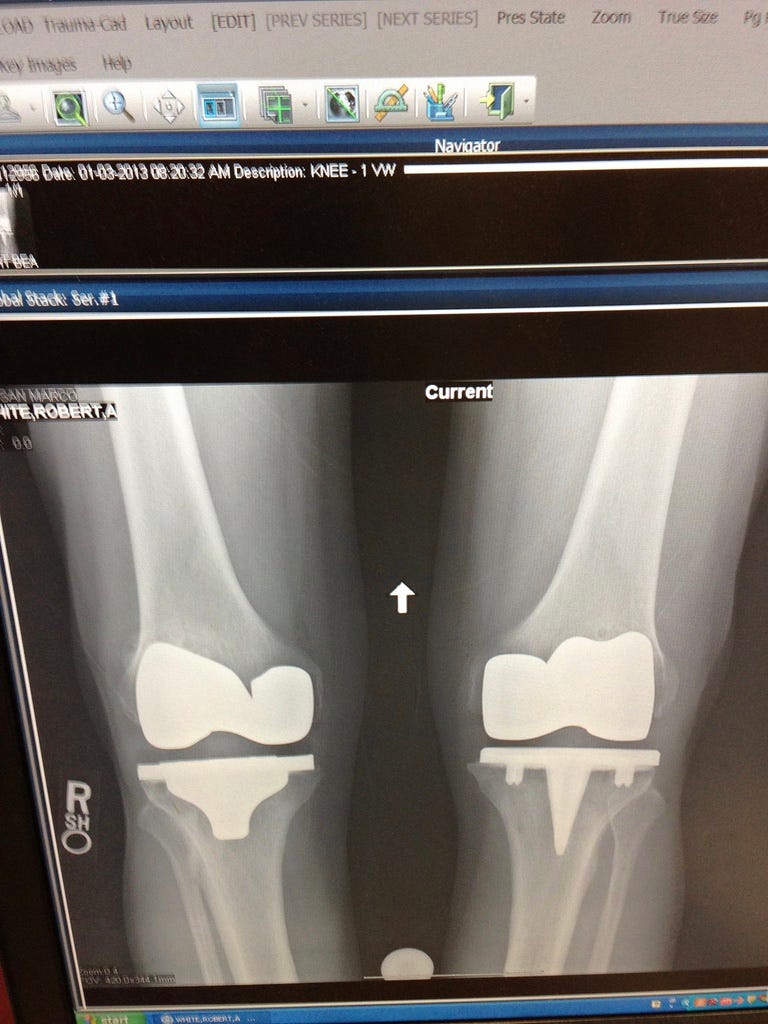

That said, it’s true that I wrecked my knees from all that running. So? I got me some new knees! See? —